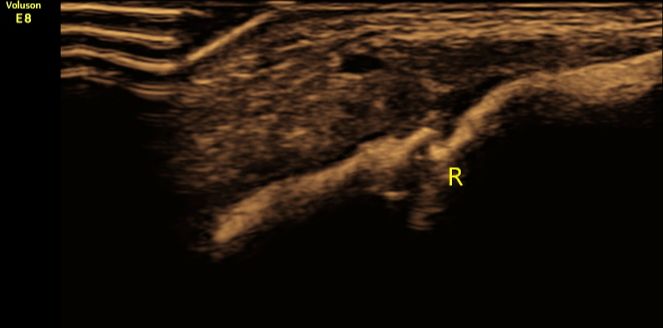

(图1:超声二维清晰显示右侧锁骨骨折断端,骨皮质连续性中断、断端错位。)

①直接征象:超声二维显示锁骨骨皮质连续性中断,新鲜错位骨折时断端显示清晰,愈合期骨折处显示增厚、模糊;